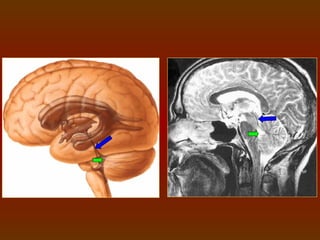

TERCEIRO VENTRÍCULO

 Cada ventrículo lateral conecta-se ao terceiro ventrículo através de um

forame interventricular.

 Localizado logo abaixo do nível dos ventrículos laterais.

 No teto da parte posterior está localizada a glândula pineal.

 Possui a forma grosseira de um quadrado.